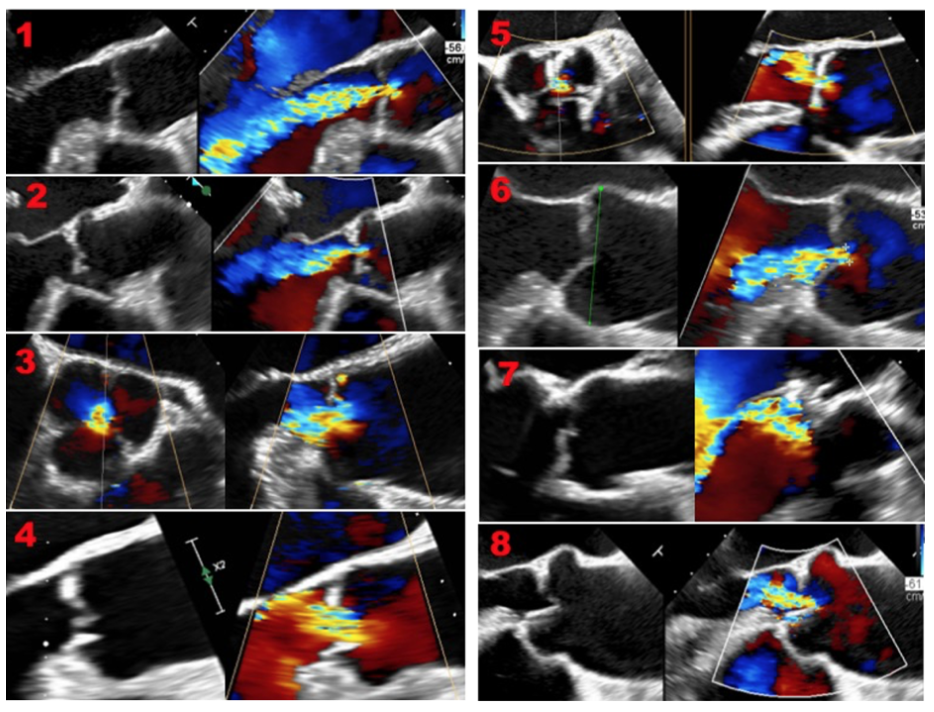

Procedural details of TAVI for AR. TAVI was performed in a hybrid operation room under general anesthesia and using intraprocedural transesophageal echocardiography fusion imaging technique (Figure 1). The technique allows the overlaying of 2D- and 3D-echocardiography on fluoroscopy and provides an ECG-gated 3D model of the heart as well. The model of the aortic valve is merged and superimposed on the fluoroscopic images, helping in defining the optimal fluoroscopic projection for the implantation as well as for the precise placement of the aortic prosthesis at the level of the annulus.10 In the absence of valve calcification (typically used as an anatomical landmark during TAVI in aortic valve stenosis), the model facilitates the correct positioning of the valve prosthesis within the annulus. The implantation itself does not differ much from the usual TAVI procedure for aortic stenosis, while the landing zone is typically high. In all patients, an Edwards SAPIEN-3 THV (Edwards LifeSciences) was used with at least 10% oversizing based on CT measurements to ensure adequate annular fixation. All procedures were performed under general anesthesia with periprocedural transesophageal echocardiography. Arterial access via the femoral artery using fluoroscopic-guided puncture and Seldinger technique was used for all cases. Rapid pacing was applied in all patients for stable and precise valve release. This was done over the left ventricular guidewire (Safari2, Boston Scientific) in all patients in order to additionally prevent the implantation of a transvenous temporary pacemaker and its possible associated complications.

The currently available THVs are designed for the treatment of calcified stenosis, relying on the fixation within an extensively calcified aortic valve annulus and cusps. In contrast in native AR, where disease often extends to structures other than the aortic valve alone and often calcification is rare, TAVI is not a common procedure. Presently, the only THV with CE approval for pure AR is the JenaValve. Overall, most TAVI cases of pure AR performed used self-expandable THVs. We are reporting our single center experience in consecutive patients with severe AR in native non or mildly-calcified valves treated with balloon-expandable Edwards Sapien-3 prosthesis. This is, to our knowledge, the largest case-series of patients with non or mildly calcified AR treated with the Edwards Sapien-3 valve. Upon adequate patient selection and consideration of the anatomical aspects of the annulus, good clinical outcome can be achieved. Even though implantation can be technically difficult due to missing anatomical landmarks, TAVI for pure AR is feasible with favorable clinical outcome in high-risk patients deemed inoperable. The use of fusion echocardiographic imaging technique, allowing the overlaying of 2D and 3D echocardiography on fluoroscopy in real time and providing an ECG-gated 3D model of the aortic valve may potentially help in defining the optimal position for device implantation in absence of calcium. This is reflected in the relative small amount of contrast agent used in this collective of patients. In our limited series, successful implantation was achieved in all patients with no device embolization or migration. Complications appear not to differ from the ones typically seen in percutaneous treatment of severe AS using the same device and includes vascular access complication as well as the need of pacemaker implantation due to high-degree AV block.